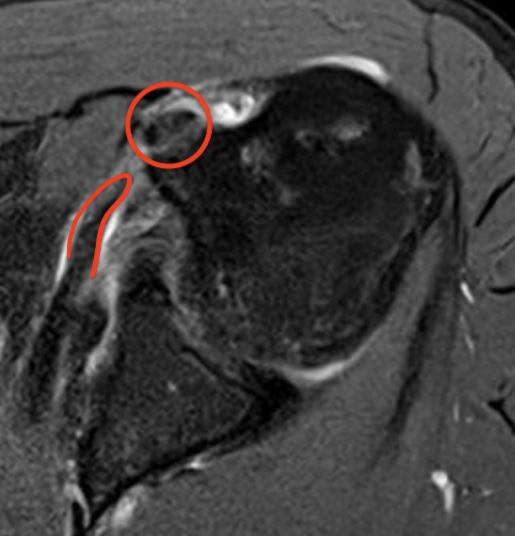

Comma sign

- medially retracted subscapularis tear

- exposes the superior insertion of superior glenohumeral ligament / coracohumeral ligament

Full thickness retracted subscapularis tear with comma sign

Full thickness completely retracted subscapularis, loss of rotator interval and comma sign

Full thickness completely retracted subscapularis, loss of rotator interval and comma sign